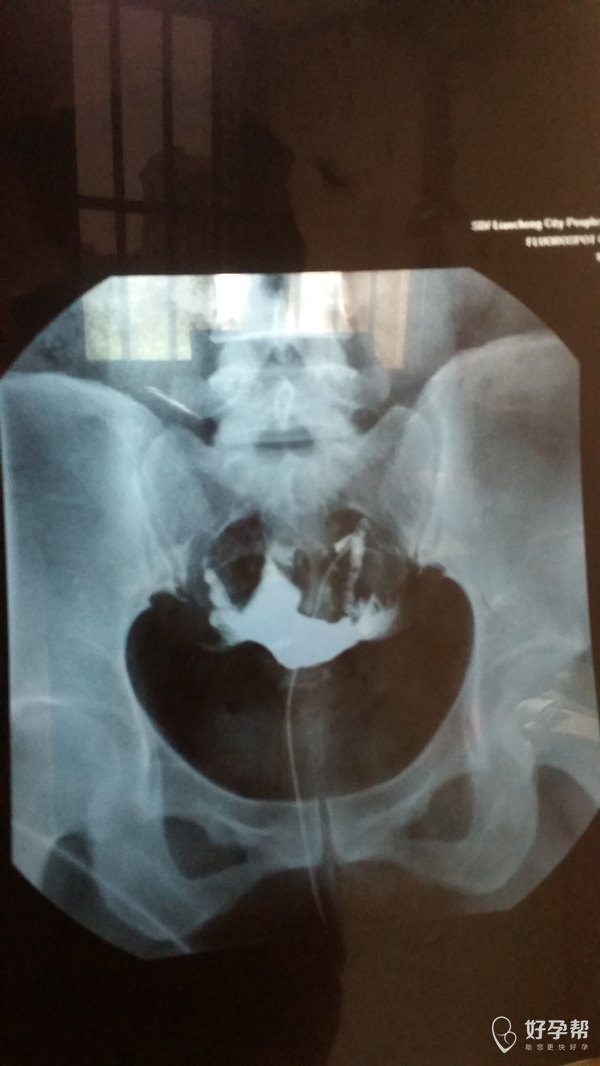

您好,双侧输卵管通畅的,但是双侧输卵管远端增粗,盆腔弥散不好,不排除盆腔粘连。